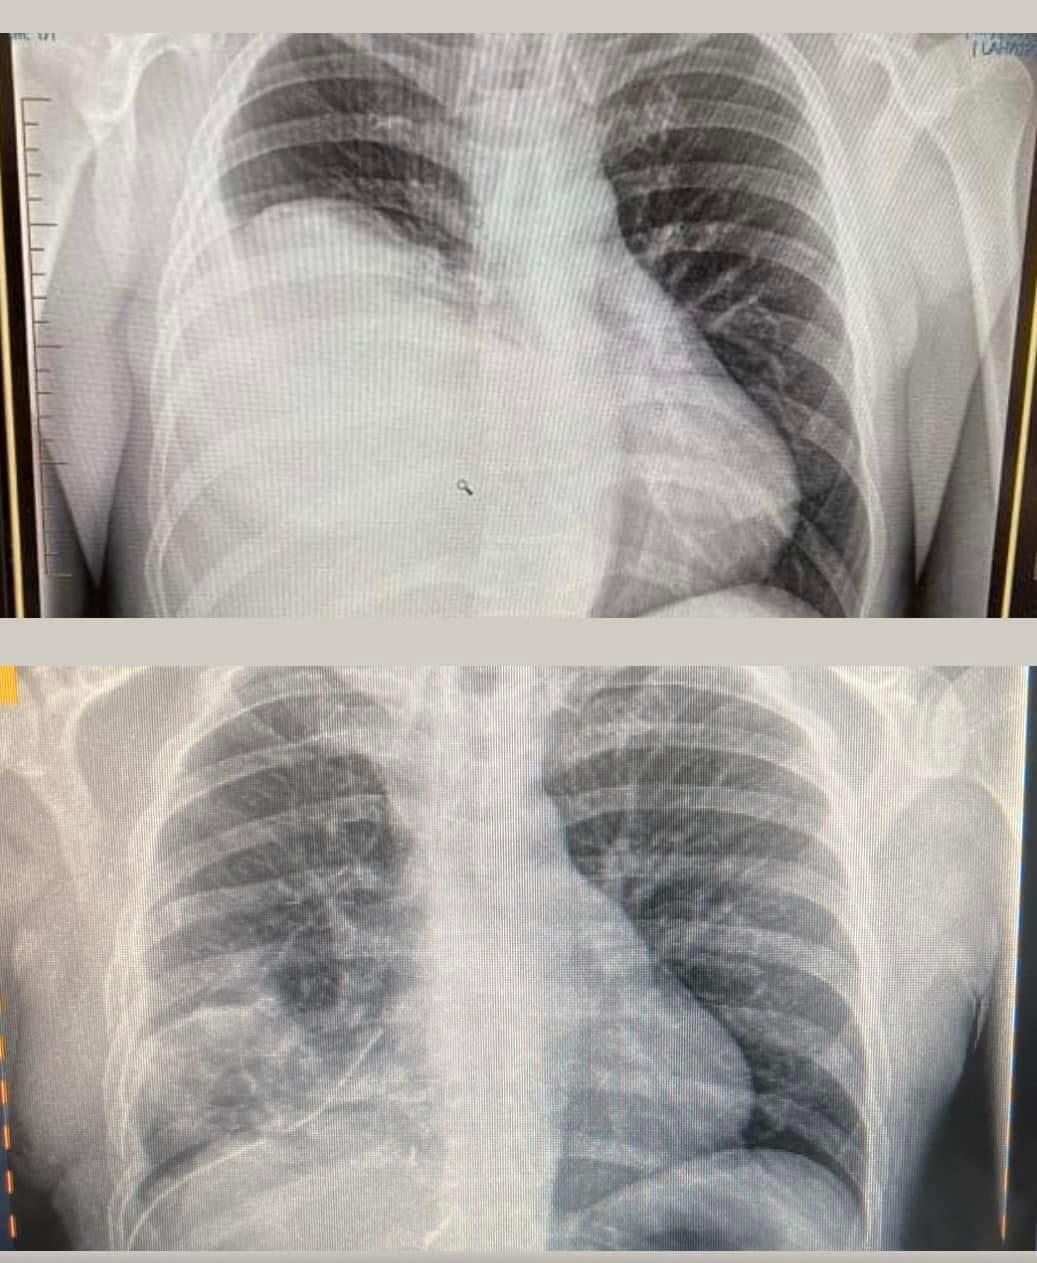

You don’t need to be a medical professional to see the difference between the very first X-ray (top) that picked up Hamish’s tumour back in August, and then the one under, around a week post op. Bloody scary I can tell you to see that for the first time 😱

By the time Hamish got to surgery, it had grown again and his right lung was completely sandwiched and non functional, and his heart had shifted and was severely compressed, more than what anyone had realised. He was lucky not to have had a cardiac event or stroke, and the specialists were blown away that he had been functioning as well as what he had.